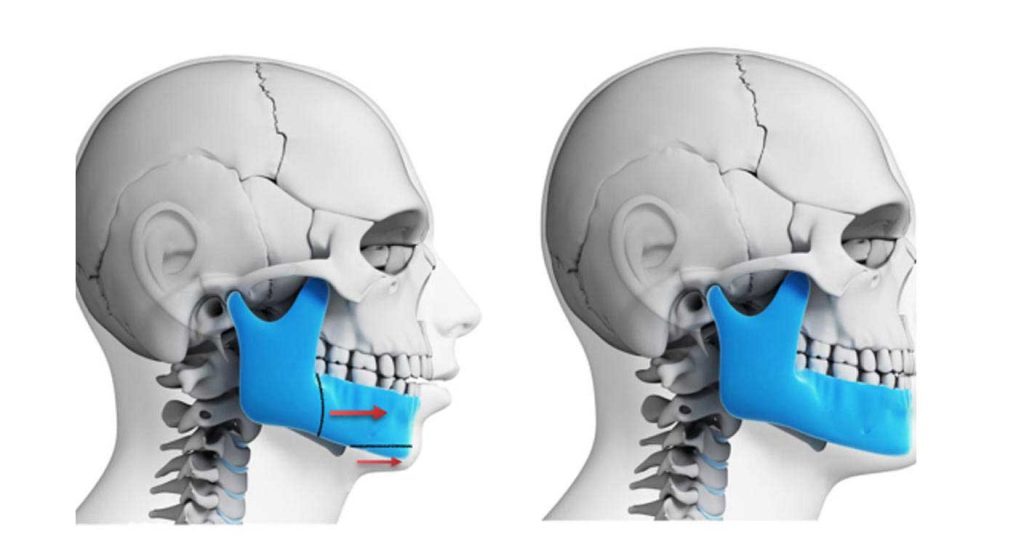

◦ آندربایت شدید (کلاس III): در این حالت که به آن جلو بودن فک پایین نیز گفته می شود، فک پایین به طور قابل توجهی جلوتر از فک بالا قرار دارد.

◦ اورجت شدید (کلاس II): در این ناهنجاری، که به آن دندان های بیرون زده نیز می گویند، فک بالا بسیار جلوتر از فک پایین است.

- جراحی فک بالا (استئوتومی Le Fort I)

در این جراحی، جراح برشی در استخوان فک بالا (ماگزیلا) ایجاد می کند تا کل فک بالا را به صورت یک واحد واحد به موقعیت صحیح خود حرکت دهد. - جراحی فک پایین (استئوتومی ساژیتال دو طرفه)

این رایج ترین نوع است که برای اصلاح موقعیت فک پایین (مندیبل) انجام می شود و فک به سمت جلو یا عقب حرکت داده می شود. - جراحی دو فک